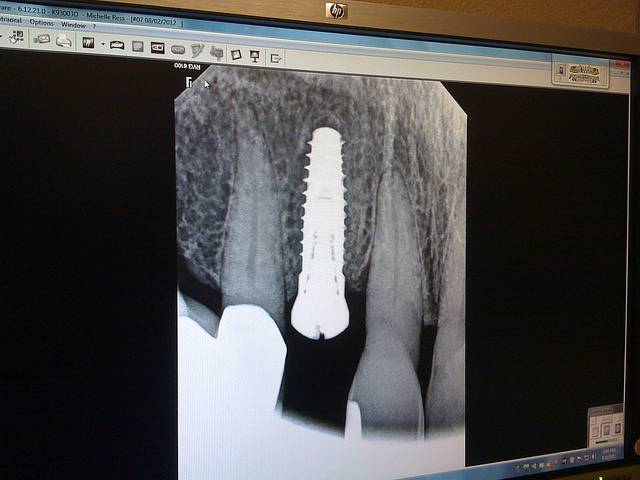

O implante dentário vem para substituir um ou mais dentes, às vezes todos, que estão ausentes na boca.

A presença deste novo elemento não só promove um sorriso mais estético, como melhora a qualidade de vida de quem o tem, uma vez que também devolve a eficiência mastigatória.

Sua instalação é realizada através de cirurgia e, como toda cirurgia, merece atenção.